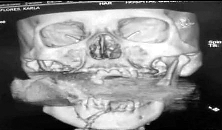

X光扫描图显示,一枚手榴弹卡在了弗洛雷斯的上下颌骨之间。

当弗洛雷斯醒来时,她已被送到了医院。医生们一开始还以为弗洛雷斯的脸部受到了石块的重击,但在进行X光扫描后发现,在她的上下颌骨之间卡着一枚未爆炸的手榴弹。有关专家判断,该手榴弹是经过发射器投掷的,一旦被引爆将会危及周围十米以内的人员。